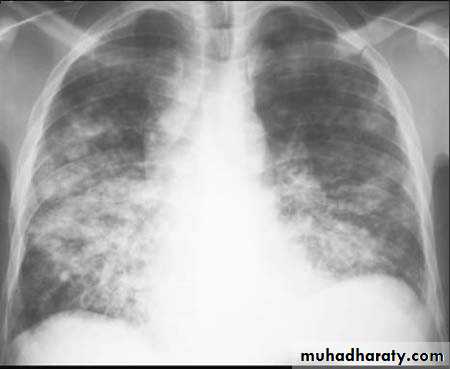

Bronchopneumonia

Pleural pain is uncommon

Chest X-ray shows mottled opacities in both lung fields, chiefly in the lower zones.